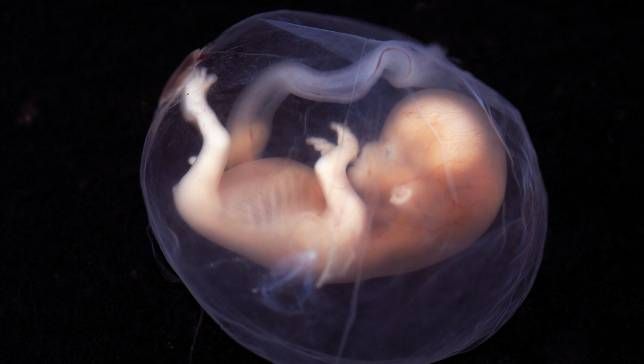

Na imagem acima, podemos ver a ressonância magnética de um feto de 20 semanas e o outro de 40. São imagens fornecidas pela Faculdade de Medicina da Universidade Estatal de Wayne (Michigan, Estados Unidos) que ilustram com clareza como é a atividade cerebral destes dois bebês no útero de sua mãe.